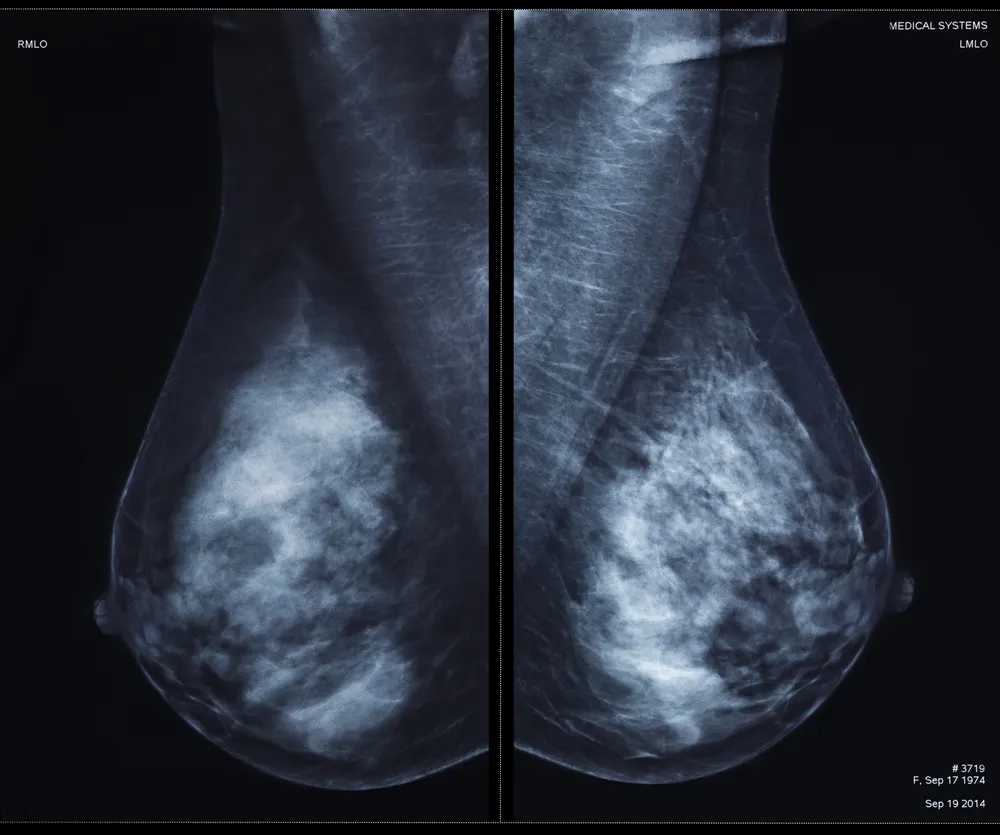

پس از انجام ماموپلاستی، بهویژه در زنان بالای ۴۰ سال، انجام غربالگریهای دورهای مانند ماموگرافی و سونوگرافی سینه اهمیت ویژهای دارد. این بررسیها نهتنها در تشخیص زودهنگام ضایعات احتمالی مؤثرند، بلکه به اطمینان از سلامت بافت بازسازیشده نیز کمک میکنند.

یکی از مزایای غیر مستقیم ماموپلاستی کوچکسازی، افزایش دقت ماموگرافی است. با کاهش حجم بافت سینه، نواحی مشکوک در تصویربرداری راحتتر قابلمشاهده میشوند.

به همین دلیل، برخی پژوهشها نشان دادهاند که در زنانی که تحت این جراحی قرار گرفتهاند، سرطانهای احتمالی در مراحل اولیه و با حجم کوچکتر تشخیص داده میشوند، که این امر تأثیر مستقیم بر افزایش نرخ بقا دارد.

انجام ماموگرافی، سونوگرافی پستان یا MRI پیش از جراحی الزامی است تا هرگونه ضایعه مشکوک در بافت سینه شناسایی شود.